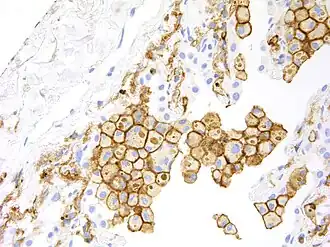

HAVCR2 expression is up regulated in tumor-infiltrating lymphocytes in lung,[8] gastric,[30] head and neck cancer,[31] schwannoma,[32] melanoma[33] and follicular B-cell non-Hodgkin lymphoma.[34] It is also up-regulated in tumour-associated macrophages in various malignancies, including melanoma, especially in immunotherapy-resistant context.[9]